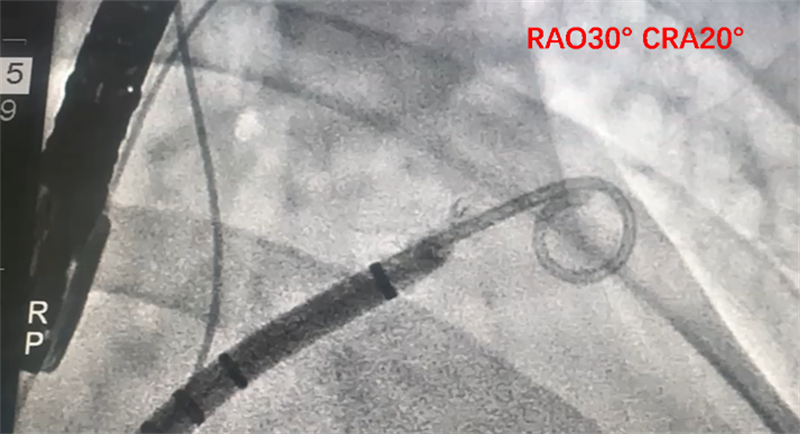

导引系统下精准封堵

双重保障 更安全 更高效

在TEE和透视引导下,徐主任团队为患者实行手术,选择靠中下稍偏后的位点进行房间隔穿刺,后在右肩及肝位分别进行左心耳造影,测心耳开口为28*31 mm,深度为27mm,因此选择植入一枚35mm WATCHMAN FLXTM封堵器,手术过程顺利。

术中进行左心耳造影及测量